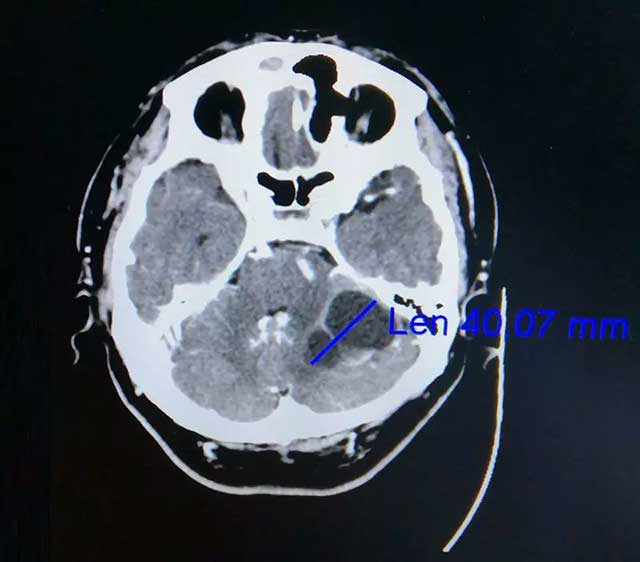

在家人陪伴下,劭阿伯到医院做了检查。查头颅CT提示:左侧小脑囊实性占位,很可能是转移瘤。后又经PET-CT检查提示:左侧小脑半球不规则囊性占位,转移可能性大,原发肿瘤待排。此时悬在劭阿伯心中的“达摩克利斯之剑”摇摇欲坠,原来两年前劭阿伯曾患肺癌,接受过放化疗。为寻求进一步治疗,劭阿伯一家慕名来到上海蓝十字脑科医院。

▲ 增强CT显示肿瘤达4公分大小